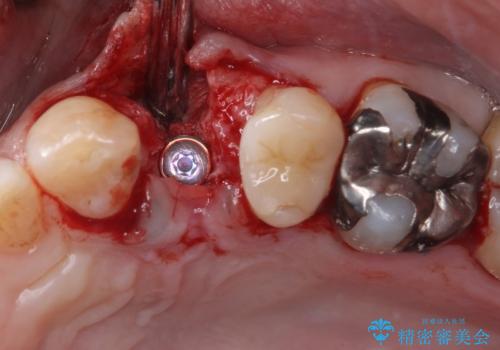

割れてしまった小臼歯 インプラントによる補綴治療

- 他院で抜歯が必要と診断され、再度診断を希望して来院された患者様です。

顕微鏡下で診察を行ったところ、歯根が垂直に破折していたため、抜糸してインプラントによる補綴治療を行うこととしました。

より審美的で、より機能的に優れた治療をご希望とのことであったので、ジルコニアカスタムアバットメントを用いたインプラント治療を行うこととしました。

インプラントは、人工骨を用いた際の骨誘導能が比較的高いとさせるストローマン社のSLActiveを使用しました。